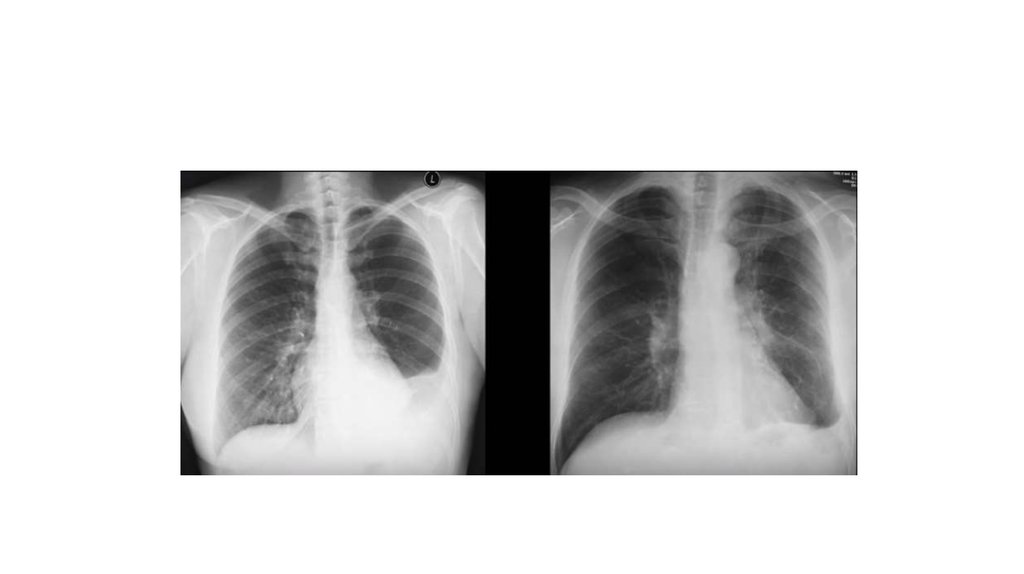

Дифференциальная диагностика заболеваний плевры